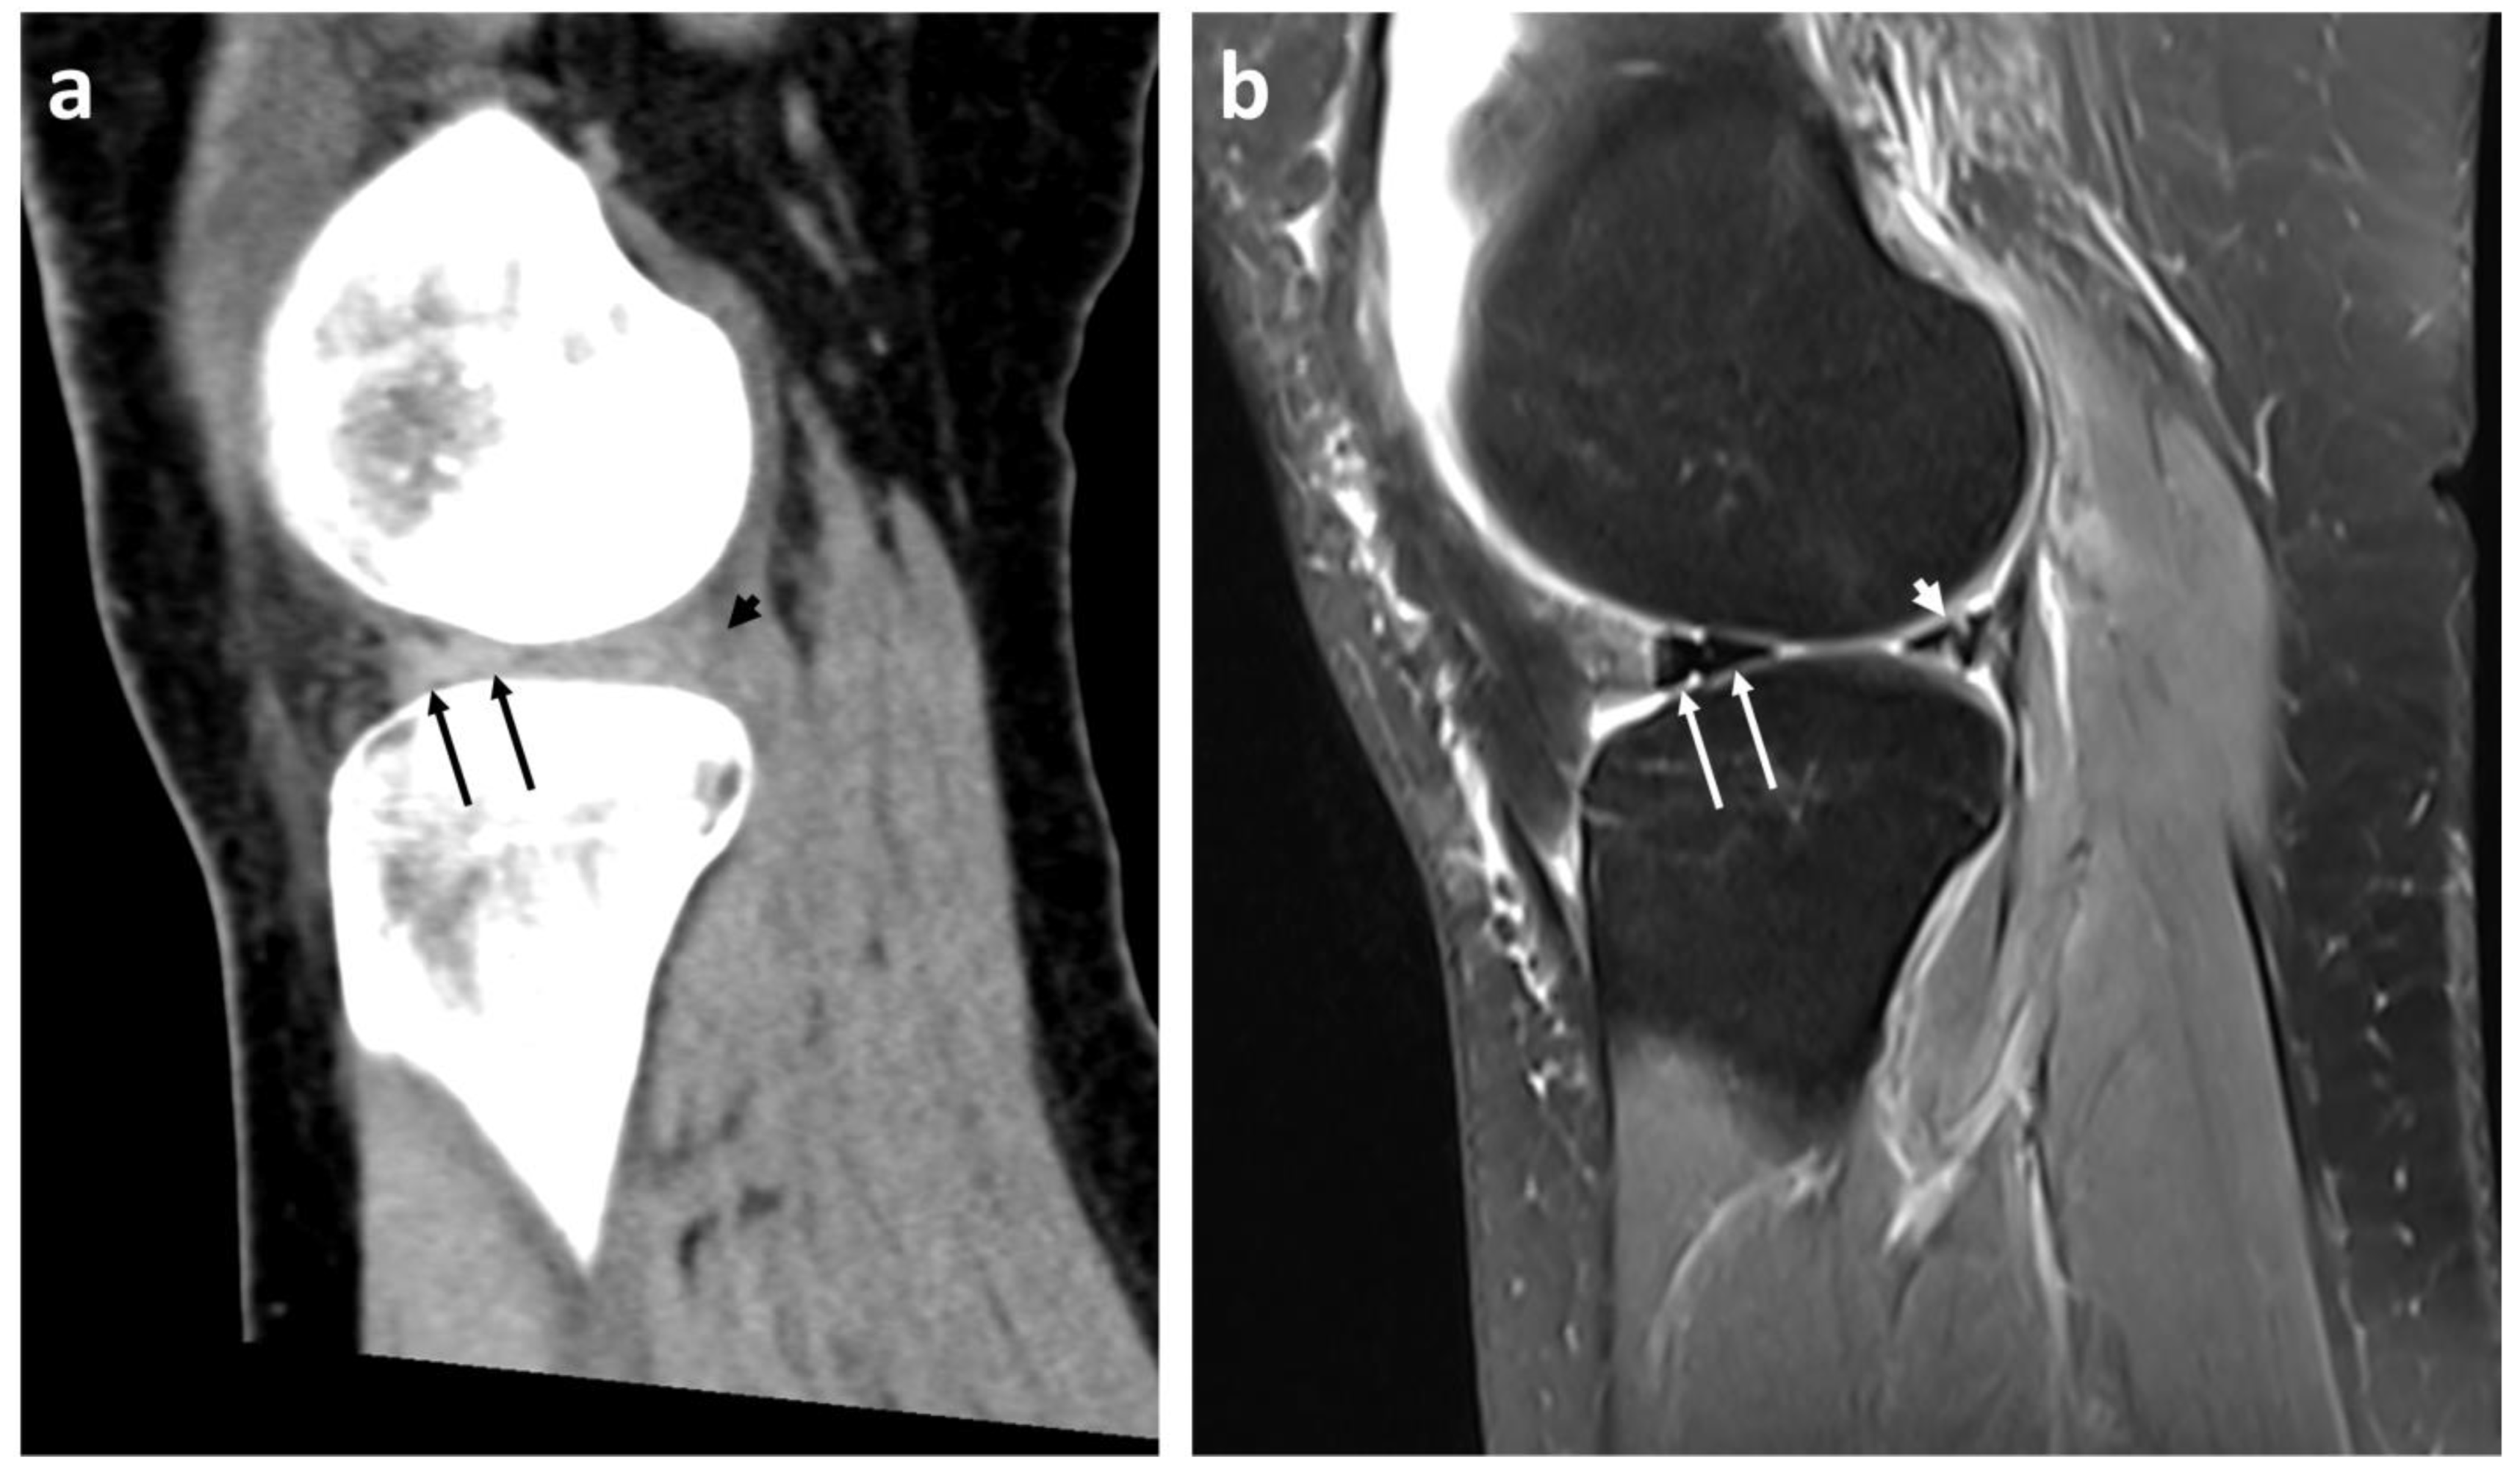

Diagnostics Free FullText Diagnostic Accuracy of 128Slice SingleSource CT for the Bucket Handle Meniscus Tear Aaos See sagittal and coronal images of the signs and signs. The meniscus can tear from acute trauma or as the result of degenerative changes that happen over time. This video provides information about the causes and symptoms of meniscus tears, surgical and nonsurgical treatment options, and. Tears are noted by how they look, as. This supplementary material provides additional information. Bucket Handle Meniscus Tear Aaos.